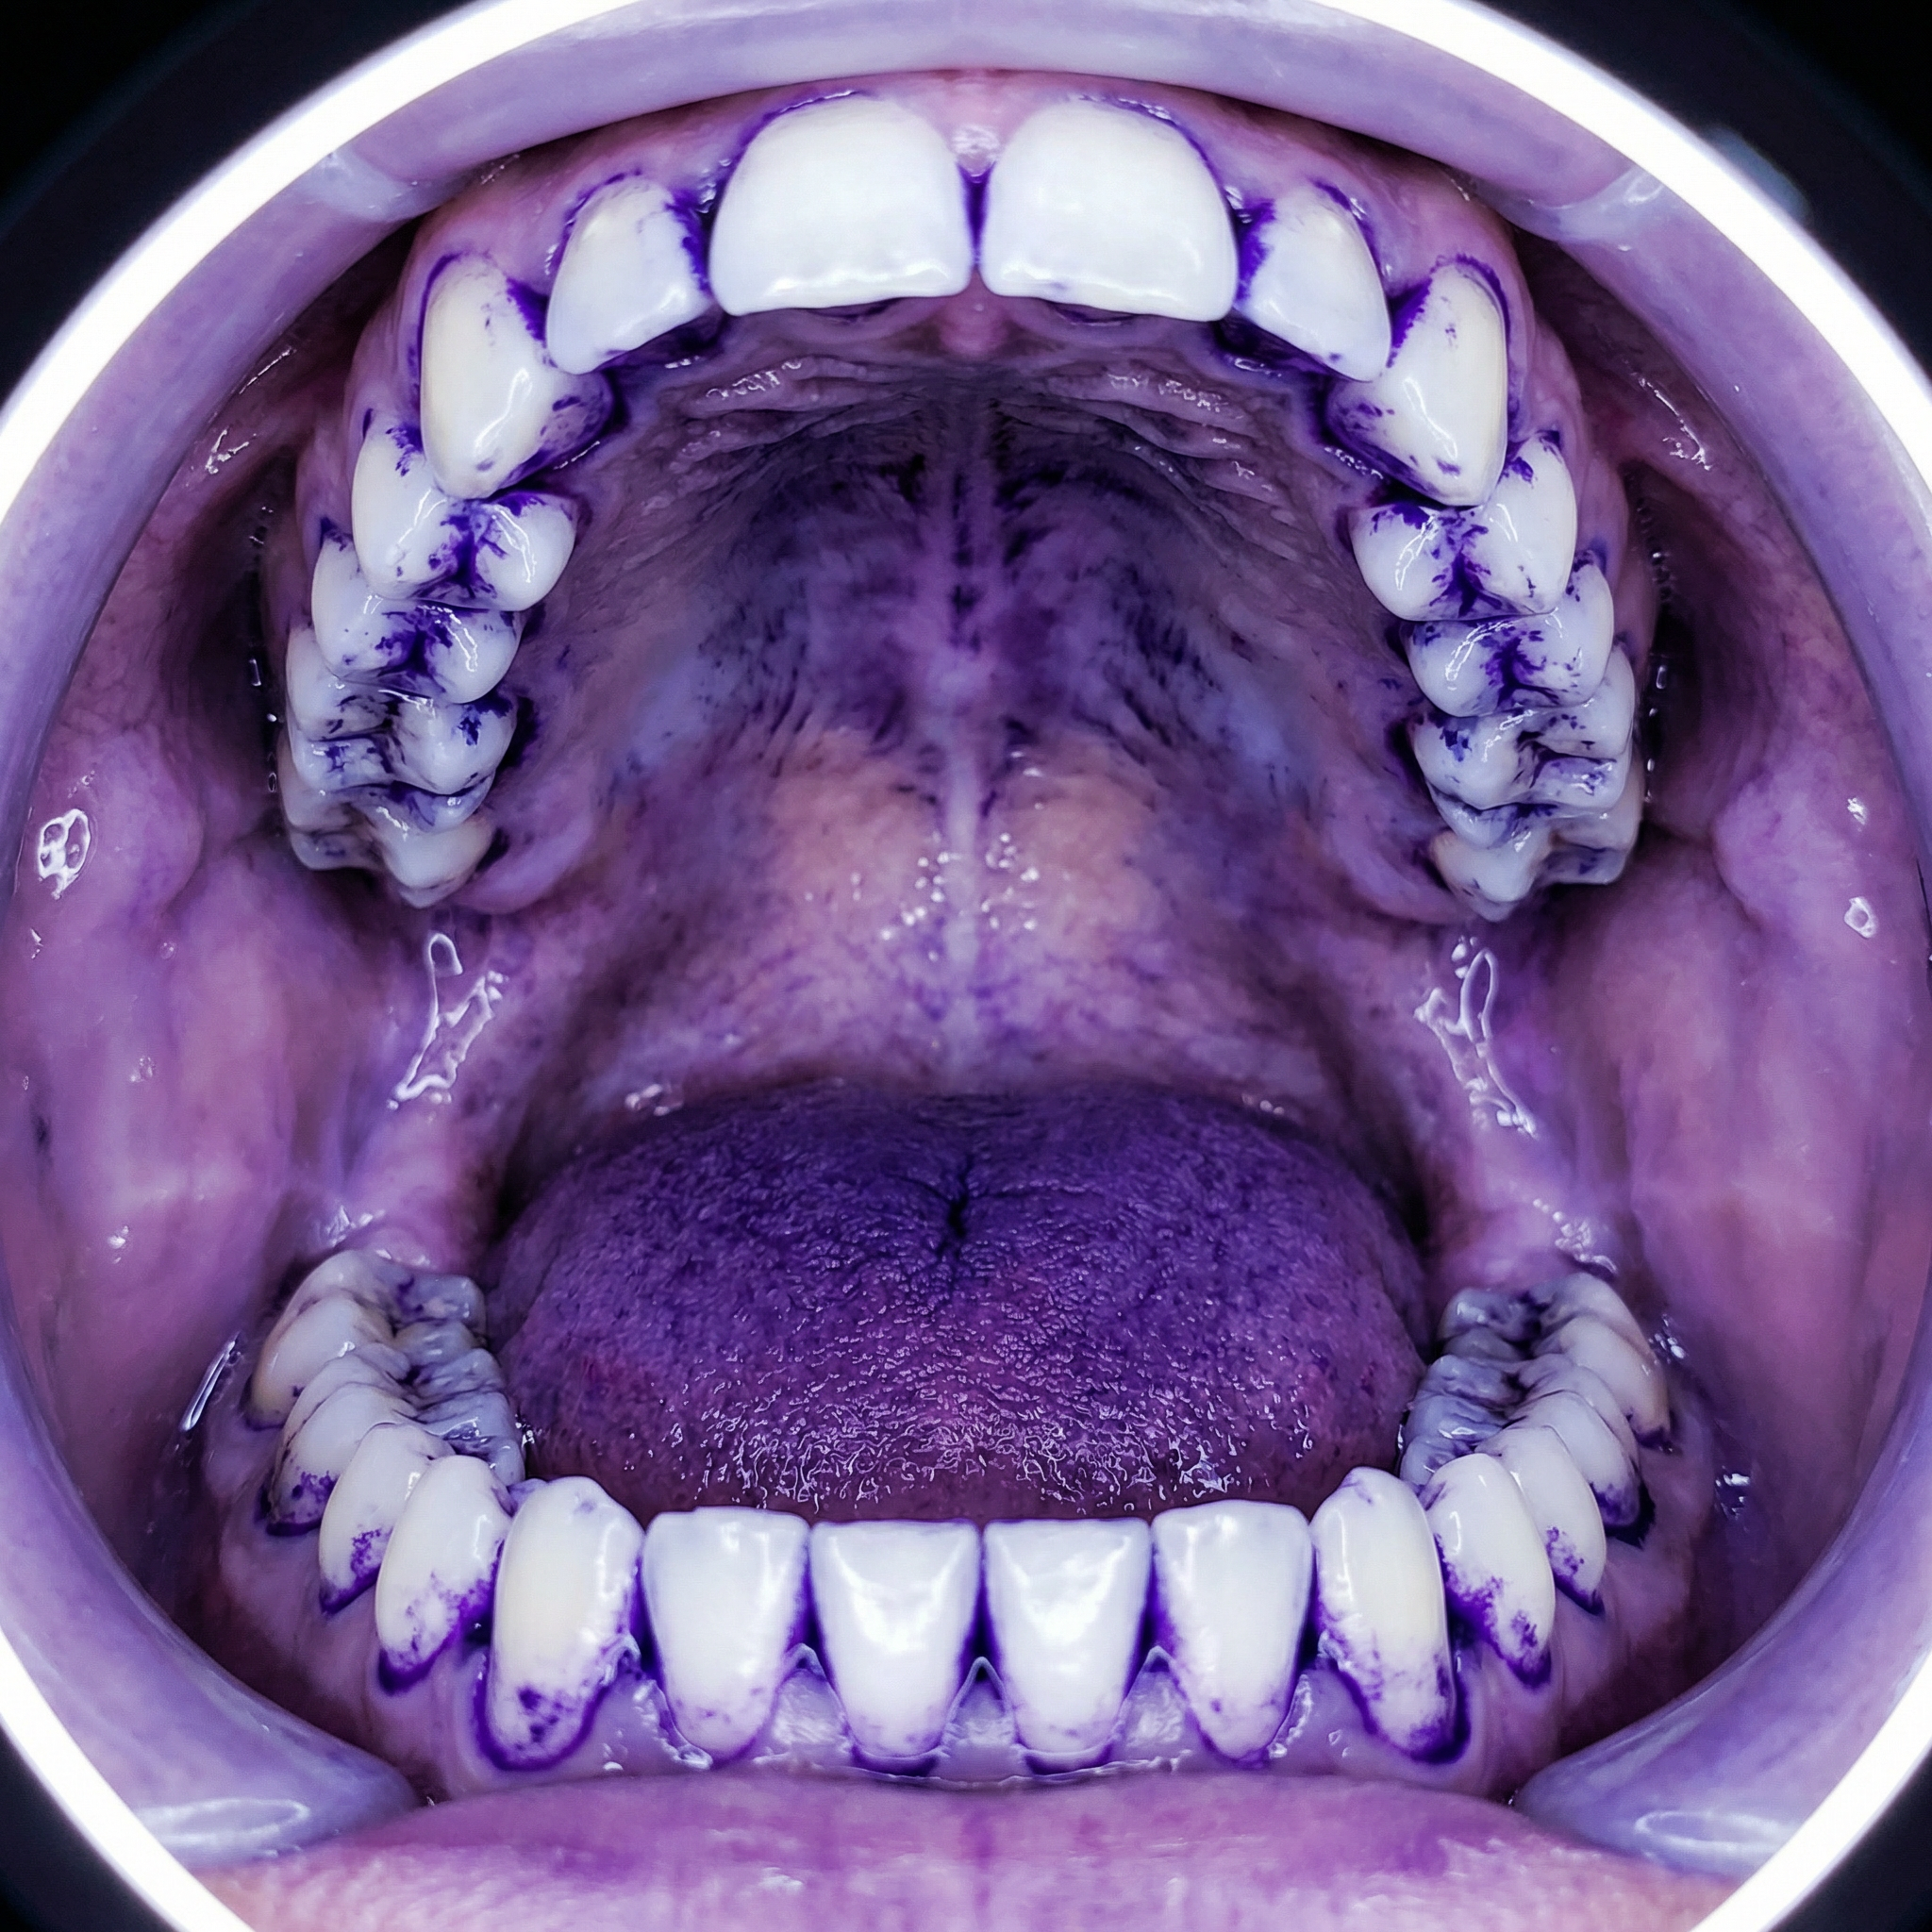

On the fifth day, let's first look at the basic progress of the biofilm construction (using a biofilm staining agent):

The nine people were then divided into three groups of three. The first group was instructed to clean their mouths using only a toothbrush; the second group was instructed to clean their mouths using only a toothbrush and a tongue scraper; and the third group was instructed to clean their mouths using only the Tongueclear oral hygiene kit. Let's look at the cleaning results:

We then collected biofilm samples from the gums, surface of the tongue, back of the tongue, inner cheeks and palate of these three groups of people and observed them under a microscope:

The results showed that when Tongueclear cleaned the mouth, biofilms on teeth, tongue, gums, upper and lower jaws and oral soft tissues could be gently removed, and breath was significantly improved—even the subjects themselves could feel that their breath became fresher.